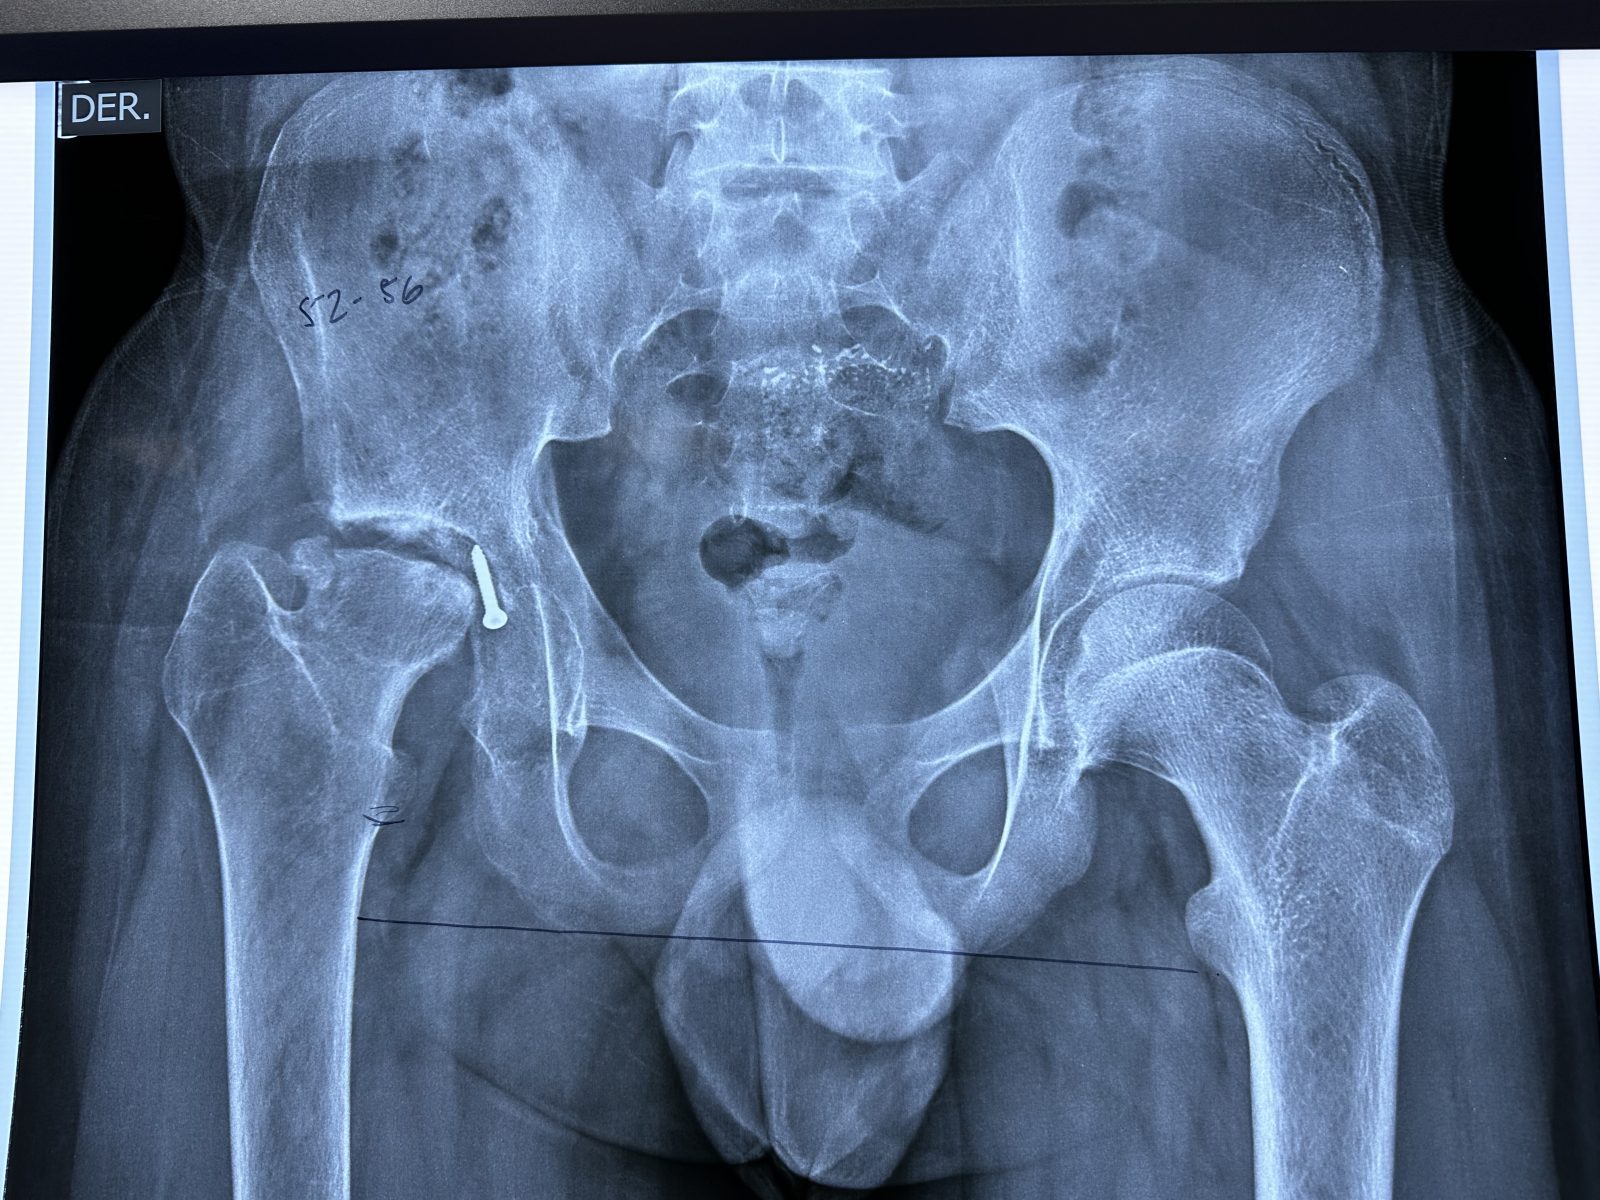

Today was also a day that highlighted, as it seems every year, just how tough, resilient and stoic the Ecuadorian people are. Just looking at their x-rays is painful enough; and watching them struggle up stairs or to get on an examination table almost physically transfers what you see – you almost feel the pain yourself. Many have a very fatalistic approach – they are so uncomfortable and can’t sleep that they both can’t wait to get their hip replacement but when taken to the operating room are afraid to sleep for fear of never waking up. In that moment they simply give themselves over to faith that it will all work out. It’s when they get to the ward when the nurses and the physios get to work that the real satisfaction begins and the step by step recovery process to a renewed life begins. That is when family, friends and patients really clap their hands together and truly thank you for the gift that our team has been able to restore – and it’s that feeling of sincere gratitude that makes all of us feel like we have done something worthwhile. It’s what brings us back year after year, giving up vacation time to feel that immense sense of pride, sense of well being and contribution.